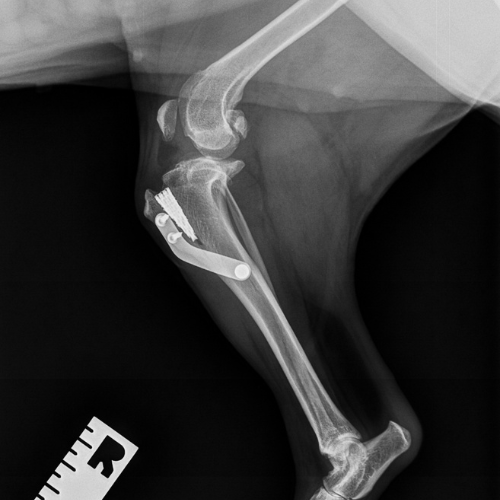

El servicio de traumatología está dirigido por Enrique Senís, especialista en traumatología y ortopedia por la Universidad Complutense de Madrid . Estamos orientados al diagnóstico y tratamiento de patologías del sistema musculoesquelético, incluyendo fracturas, luxaciones, rotura de ligamento cruzado y demás alteraciones articulares y deformidades óseas.

Disponemos de medios diagnósticos avanzados y aplicamos técnicas quirúrgicas de última generación en osteosíntesis, estabilización articular y corrección de deformidades, con el objetivo de restaurar la funcionalidad y minimizar el dolor en nuestros pacientes.